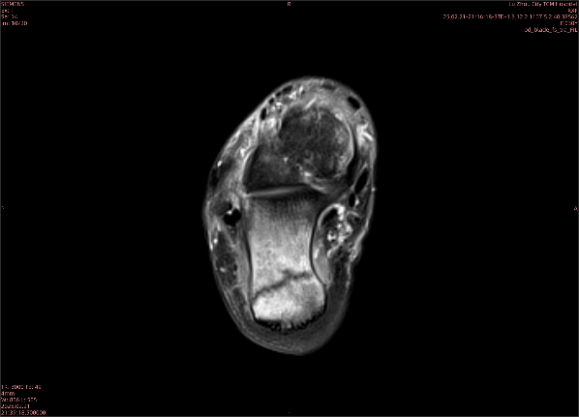

隱性骨折在MRI表現(xiàn)為T(mén)1WI序列上見(jiàn)由關(guān)節(jié)面向骨干走行的形態(tài)各異低信號(hào)區(qū),有線狀、條狀、紊亂低信號(hào),信號(hào)強(qiáng)度不均勻。與T1WI低信號(hào)改變相對(duì)應(yīng)部位在T2WI上表現(xiàn)為相應(yīng)形狀的高、低混雜信號(hào),且部分低信號(hào)周?chē)梢?jiàn)高信號(hào)水腫改變。STIR序列圖像上病灶呈顯著高信號(hào),與信號(hào)被抑制的臨近正常骨髓形成鮮明對(duì)比,分界也較T2WI成像更為清楚。脂肪組織抑制技術(shù)是MRI的一個(gè)重要性能,脂肪抑制技術(shù)在MRI應(yīng)用中可以改善組織對(duì)比和增加病變顯示機(jī)會(huì),這樣骨髓的脂肪抑制后就不會(huì)有任何信號(hào),而隱性骨折線及骨髓水腫的異常高信號(hào)就會(huì)更加明顯的顯示出來(lái)。

舉例圖像

專業(yè)解釋看不懂沒(méi)關(guān)系,大家看圖1和圖2就可以了,這是同一個(gè)患者跟骨的磁共振和CT圖像,圖1的紅色箭頭指示的黑線就是磁共振圖像顯示的骨折線,一目了然。而對(duì)比圖2的CT圖像上并未顯示異常。